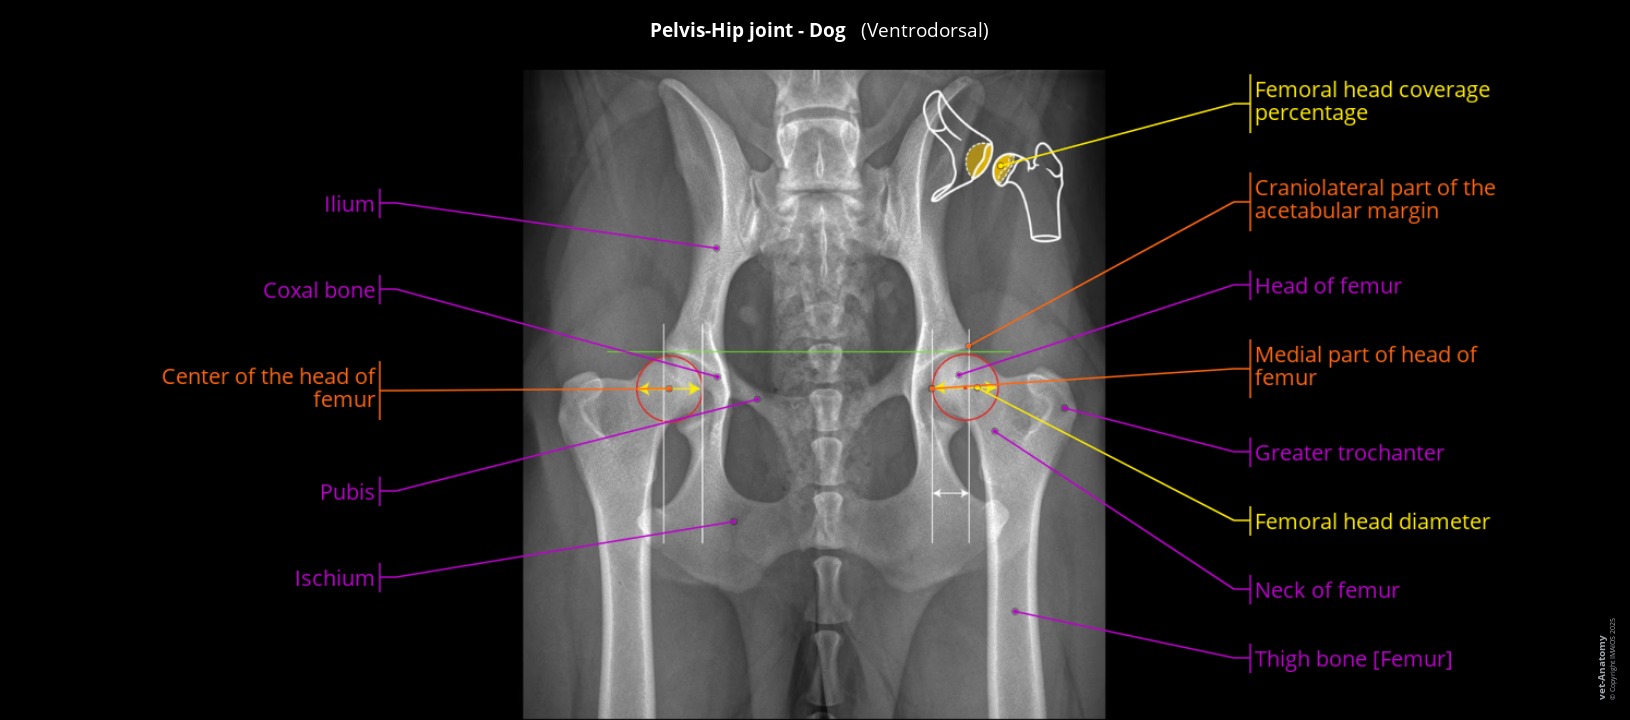

Atlas of radiological anatomy of the dog's hip

Dorsoventral radiograph of the dog's hip showing the angles of the coxofemoral joint and the diameter of the head of the femur.